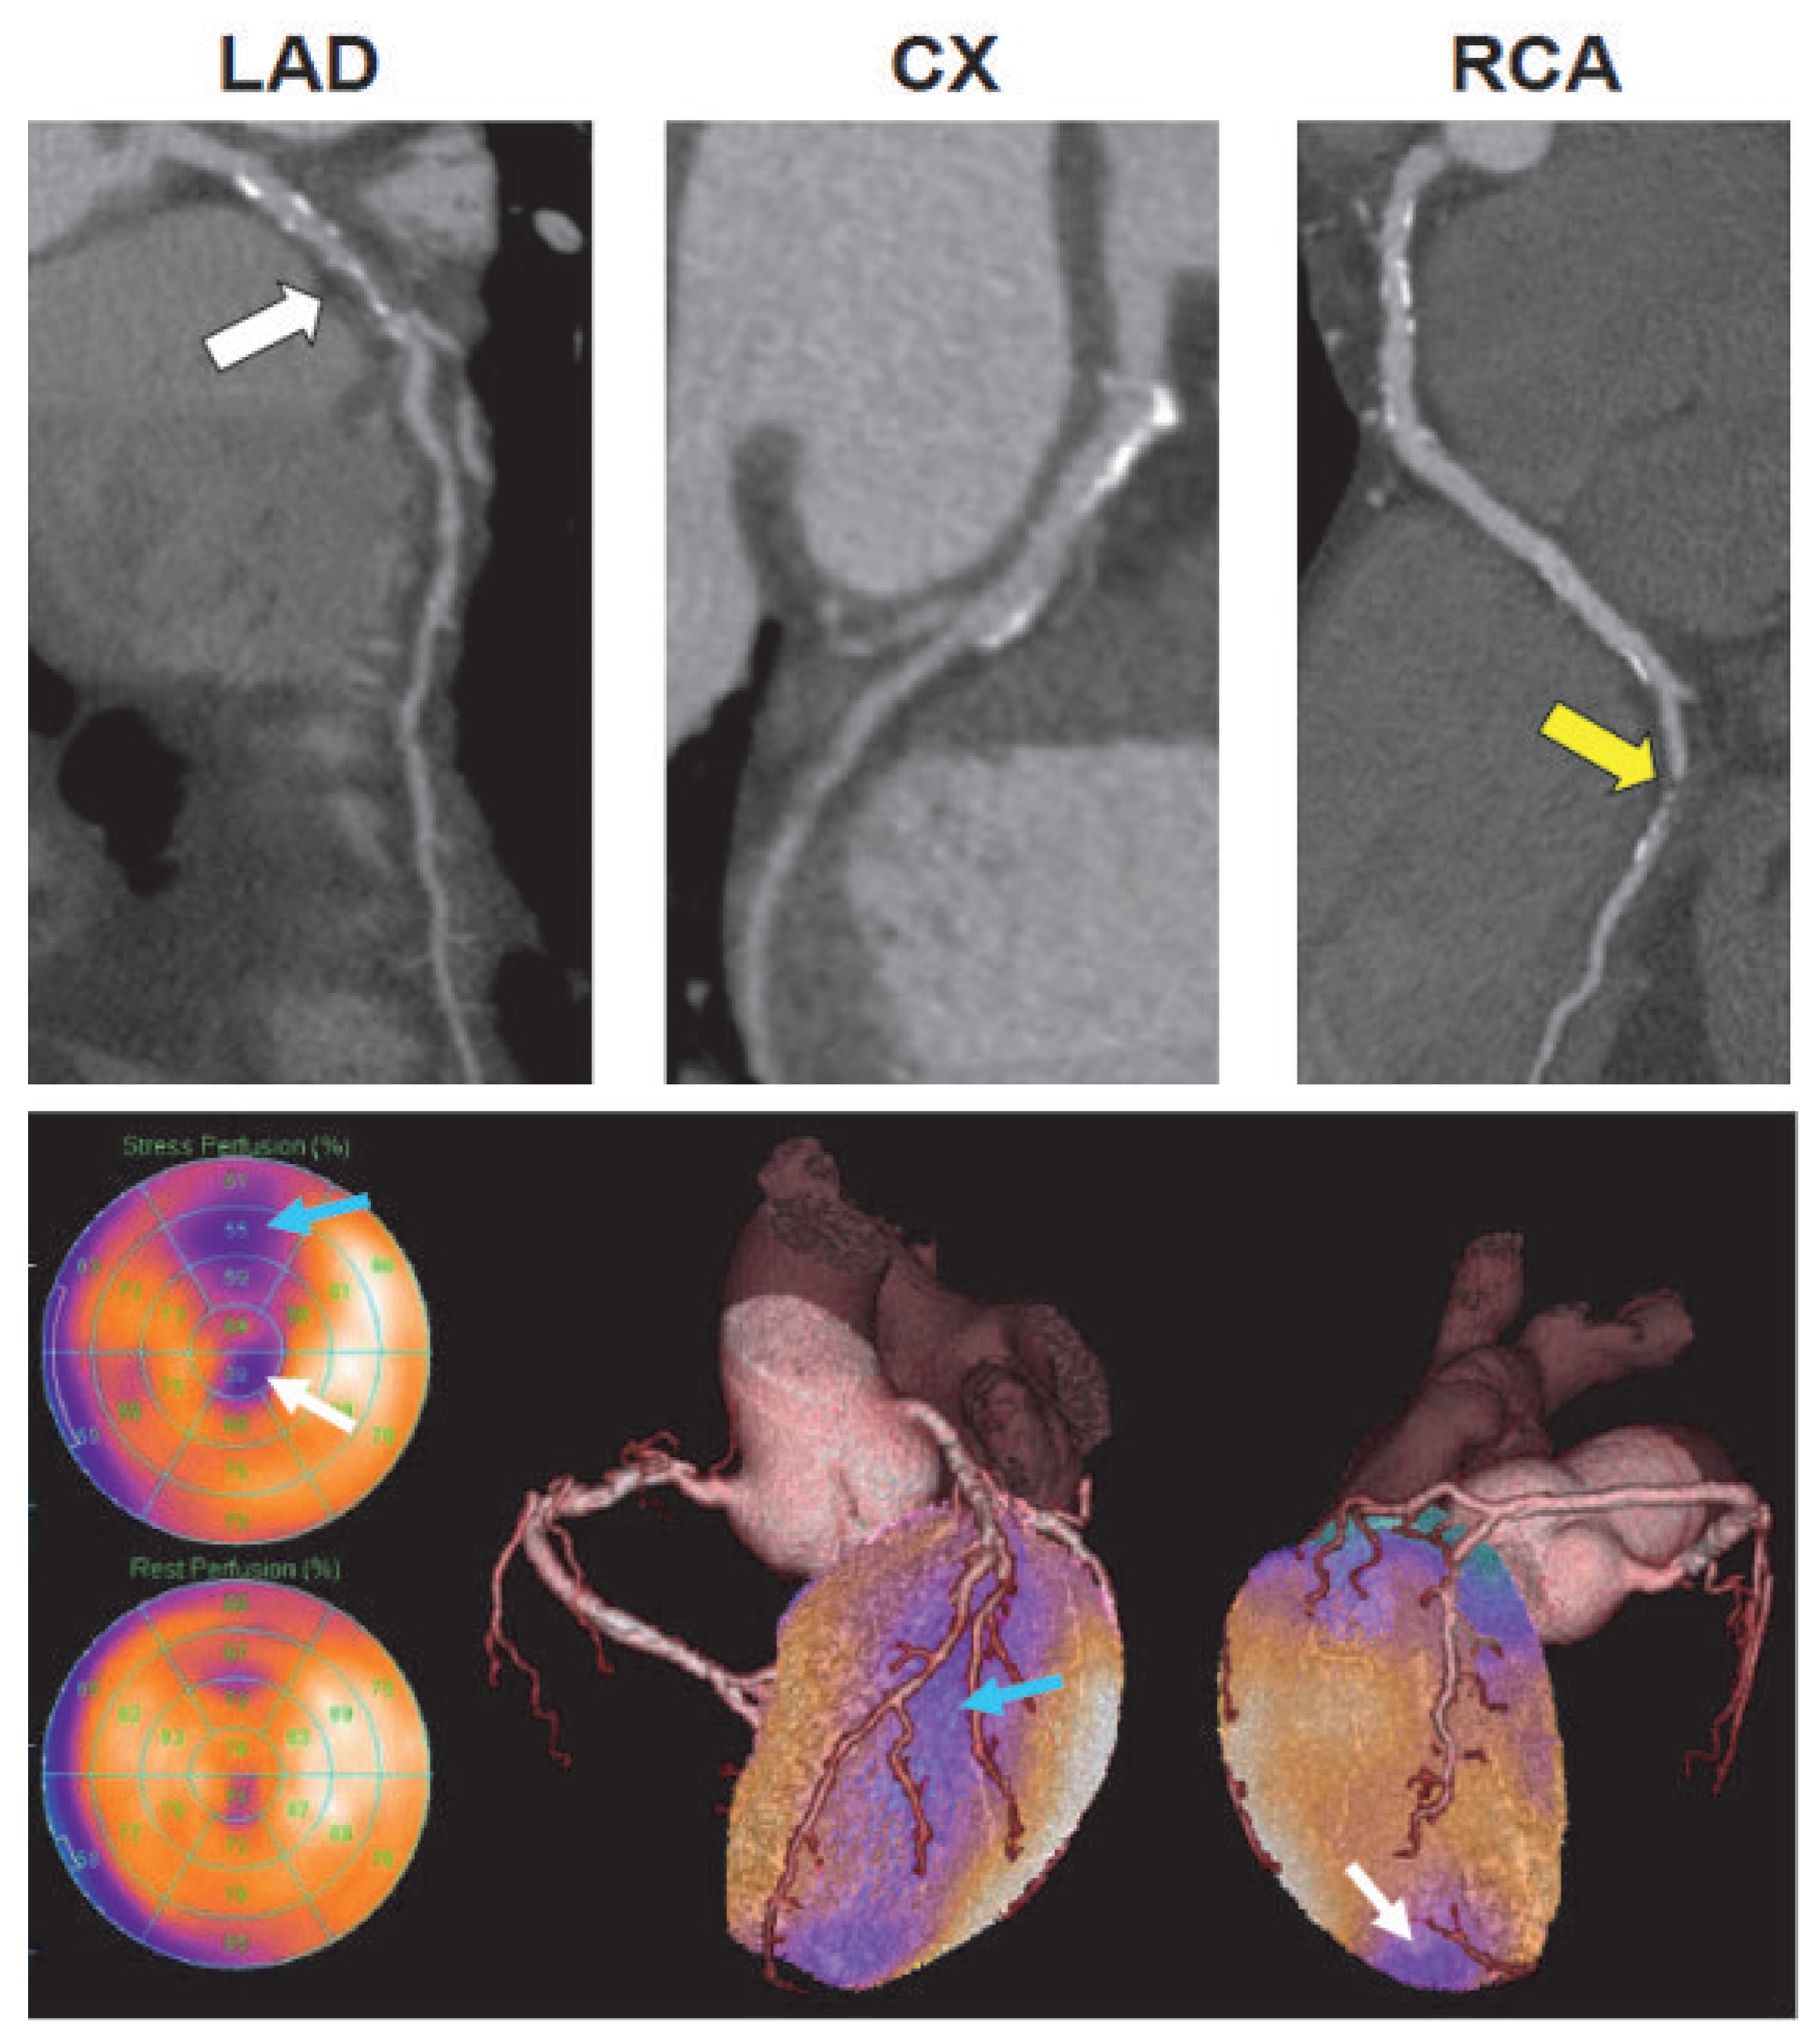

![]() |